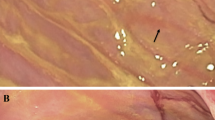

Qualitative and quantitative changes after RYGB in Phox2b-Cre-tdTomato mice. (a) Table summarizing relative changes in the amount of vagal innervation in different gut segments and glucostatic organs in non-operated, sham and RYGB animals. The relative density of fiber innervation based on the visual survey of the tissue was categorized using the following density scale: +++, high density; ++, moderate density; +, low density; +/−, inconsistent or absence of fluorescence. (b) Quantification of vagal supply to the myenteric plexus in non-operated, sham and RYGB animals. Innervation to both proximal and distal stomach is significantly reduced in RYGB mice compared with other groups. (c–j) Representative images of the gastrointestinal wall (whole mounts) in different segments of the gut. Briefly, a significant reduction of the vagal innervation to the stomach, as well as signs of neurodegeneration were noticed after RYGB. However, the vagal innervation to other segments and glucostatic organs was largely intact. Scale: 50 μm in (c) and applies through (f), 100 μm in (j). m, muscularis; n/a, non-applicable; ***P<0.05 by one-way Anova, followed by Bonferroni test. Other abbreviations are indicated in (a).

A considerable loss of innervation occurred at all sites of surgical manipulation including at the gastrojenunostomy, jejunojejunostomy and adjacent to the site of gastric clipping on both the proximal and distal stomach (Figures 2a and b). Adjacent to the above sites of surgery, the normal appearance of the myenteric plexus was often disrupted, and free-ending bundles of fibers were found in the muscularis compared with the normal appearance of their anatomical equivalents in sham and non-operated animals (Figures 2c–f). In sham animals, whereas a small reduction of innervation was apparent in the stomach adjacent to the site of gastrotomy and repair, as well as at the site of jejunostomy and repair, most of the remainder of gastrointestinal innervation was intact (Figures 2a and g). In RYGB mice, changes in innervation were not apparent in other gut segments (Figures 2a) or in the liver, gallbladder or pancreas (Figure 2a). Lastly, morphological anomalies of vagal fibers were frequently observed in the myenteric plexus and muscularis of RYGB animals, most predominantly in the stomach (Figure 2j). This included dystrophic preganglionic endings circling around myenteric neurons, and extremely swollen axons and terminals in the muscularis and adjacent nerve bundles (Figure 2j).